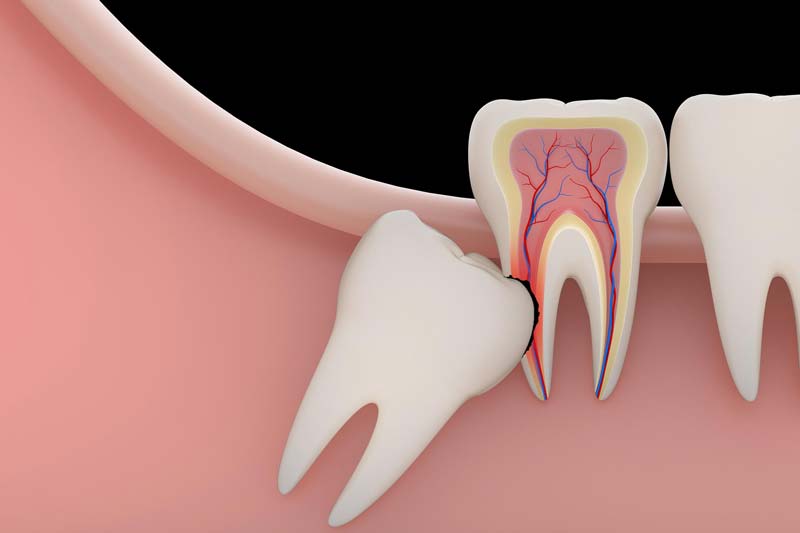

| فشار بر دندانهای مجاور | دندان عقل باعث وارد شدن فشار به دندانهای دیگر میشود که میتواند موجب آسیب به آنها گردد. |

آسیب به دندان های مجاور: در صورتی که دندان عقل به دندان های مجاور فشار بیاورد یا باعث تغییر موقعیت آنها شود، ممکن است مشکلاتی مانند شکستگی یا جابه جایی دندان های دیگر رخ دهد. این وضعیت معمولاً نیاز به جراحی فوری دارد.